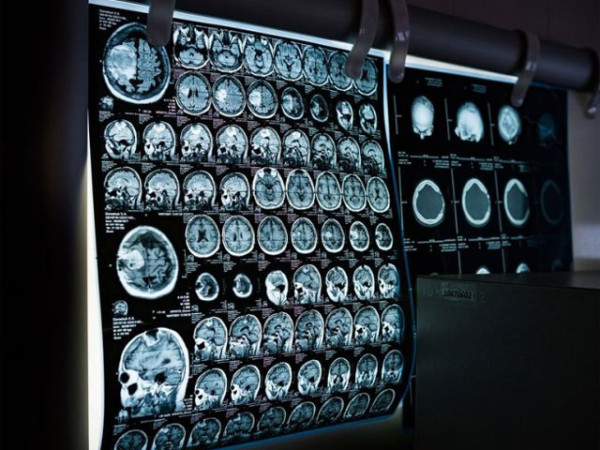

ایک نئی تحقیق میں معلوم ہوا ہے کہ بڑی عمر کے وہ افراد جنہوں نے کبھی بھی معتدل یا شدید نوعیت کی چوٹ سر پر کھائی ہو ان کی موت کی شرح چوٹ نہ لگنے والوں کی نسبت دُگنی ہوتی ہے۔

یونیورسٹی آف پینسلوینیا میں قائم پیریلمن اسکول آف میڈیسن کے محققین کو 13 ہزار افراد کے ڈیٹا کا 32 سال تک جائزہ لینے کے بعد معلوم ہوا کہ وہ افراد جن کو کسی بھی قسم کی سر کی چوٹ لگی تھی ان کی موت کی شرح چوٹ نہ لگنے والوں کی نسبت 2.21 گُنا زیادہ تھی۔

وہ افراد جن کے سر پر شدید یا متعدد چوٹیں لگیں تھیں ان کی موت کی شرح ان افراد کی نسبت سر پر چوٹ نہ لگنے والوں کی نسبت 2.87 زیادہ تھی۔

سر کی چوٹ(جو کہ عموماً گاڑی کے تصادم سے، حادثاتی طور پر گرنے سے یا کھیل میں لگتی ہیں) کا تعلق طویل مدتی صحت کے مسائل سے بھی تعلق رکھتا ہے۔ ان مسائل میں معذوری، مرگی، ڈیمینشیا اور فالج شامل ہیں۔